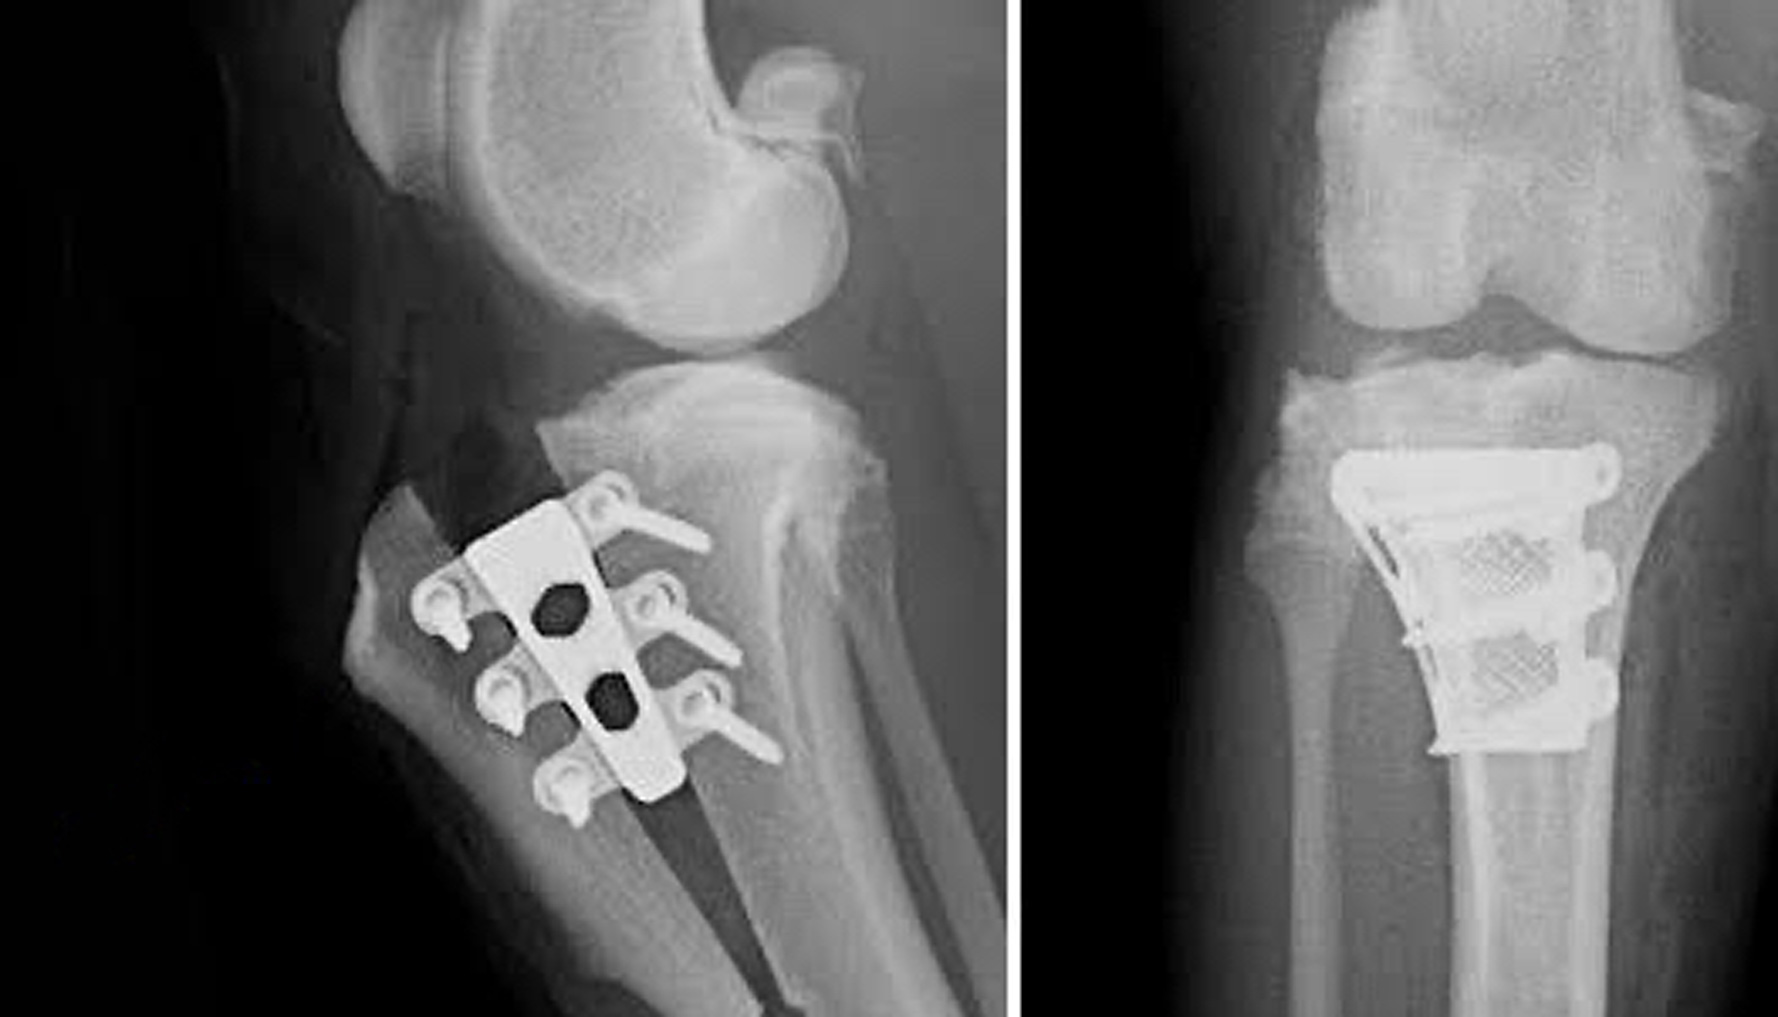

TTA is the abbreviation for Tibial Tuberosity Advancement. This a surgical procedure used to treat cranial (or anterior) cruciate ligament rupture in the knee joints (stifle) of dogs. It involves cutting the top of the shin bone (the tibia), moving it forward and stabilizing it in its new position.